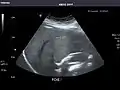

Liver

Ultrasonography of the liver with some standard measurements[6]

In patients with deranged liver function tests, ultrasound may show increased liver size (hepatomegaly), increased reflectiveness (which might, for example, indicate cholestasis), gallbladder or bile duct diseases, or a tumor in the liver.

Ultrasonography of liver tumors involves two stages: detection and characterization. Tumor detection is based on the performance of the method and should include morphometric information (three axes dimensions, volume) and topographic information (number, location specifying liver segment and lobe/lobes). The specification of these data is important for staging liver tumors and prognosis. Tumor characterization is a complex process based on a sum of criteria leading towards tumor nature definition. Often, other diagnostic procedures, especially interventional ones, are no longer necessary. Tumor characterization using the ultrasound method will be based on the following elements: consistency (solid, liquid, mixed), echogenicity, structure appearance (homogeneous or heterogeneous), delineation from adjacent liver parenchyma (capsular, imprecise), elasticity, posterior acoustic enhancement effect, the relation with neighboring organs or structures (displacement, invasion), vasculature (presence and characteristics on Doppler ultrasonography and contrast-enhanced ultrasound (CEUS).